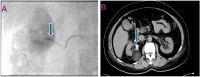

Figure 3. Intraoperative and post-procedure imaging. (A) Intraoperative fluoroscopic angiography: Blue arrow indicates the micro nester coil. (B) Postoperative CT angiogram: Blue arrow highlights the embolization coil.